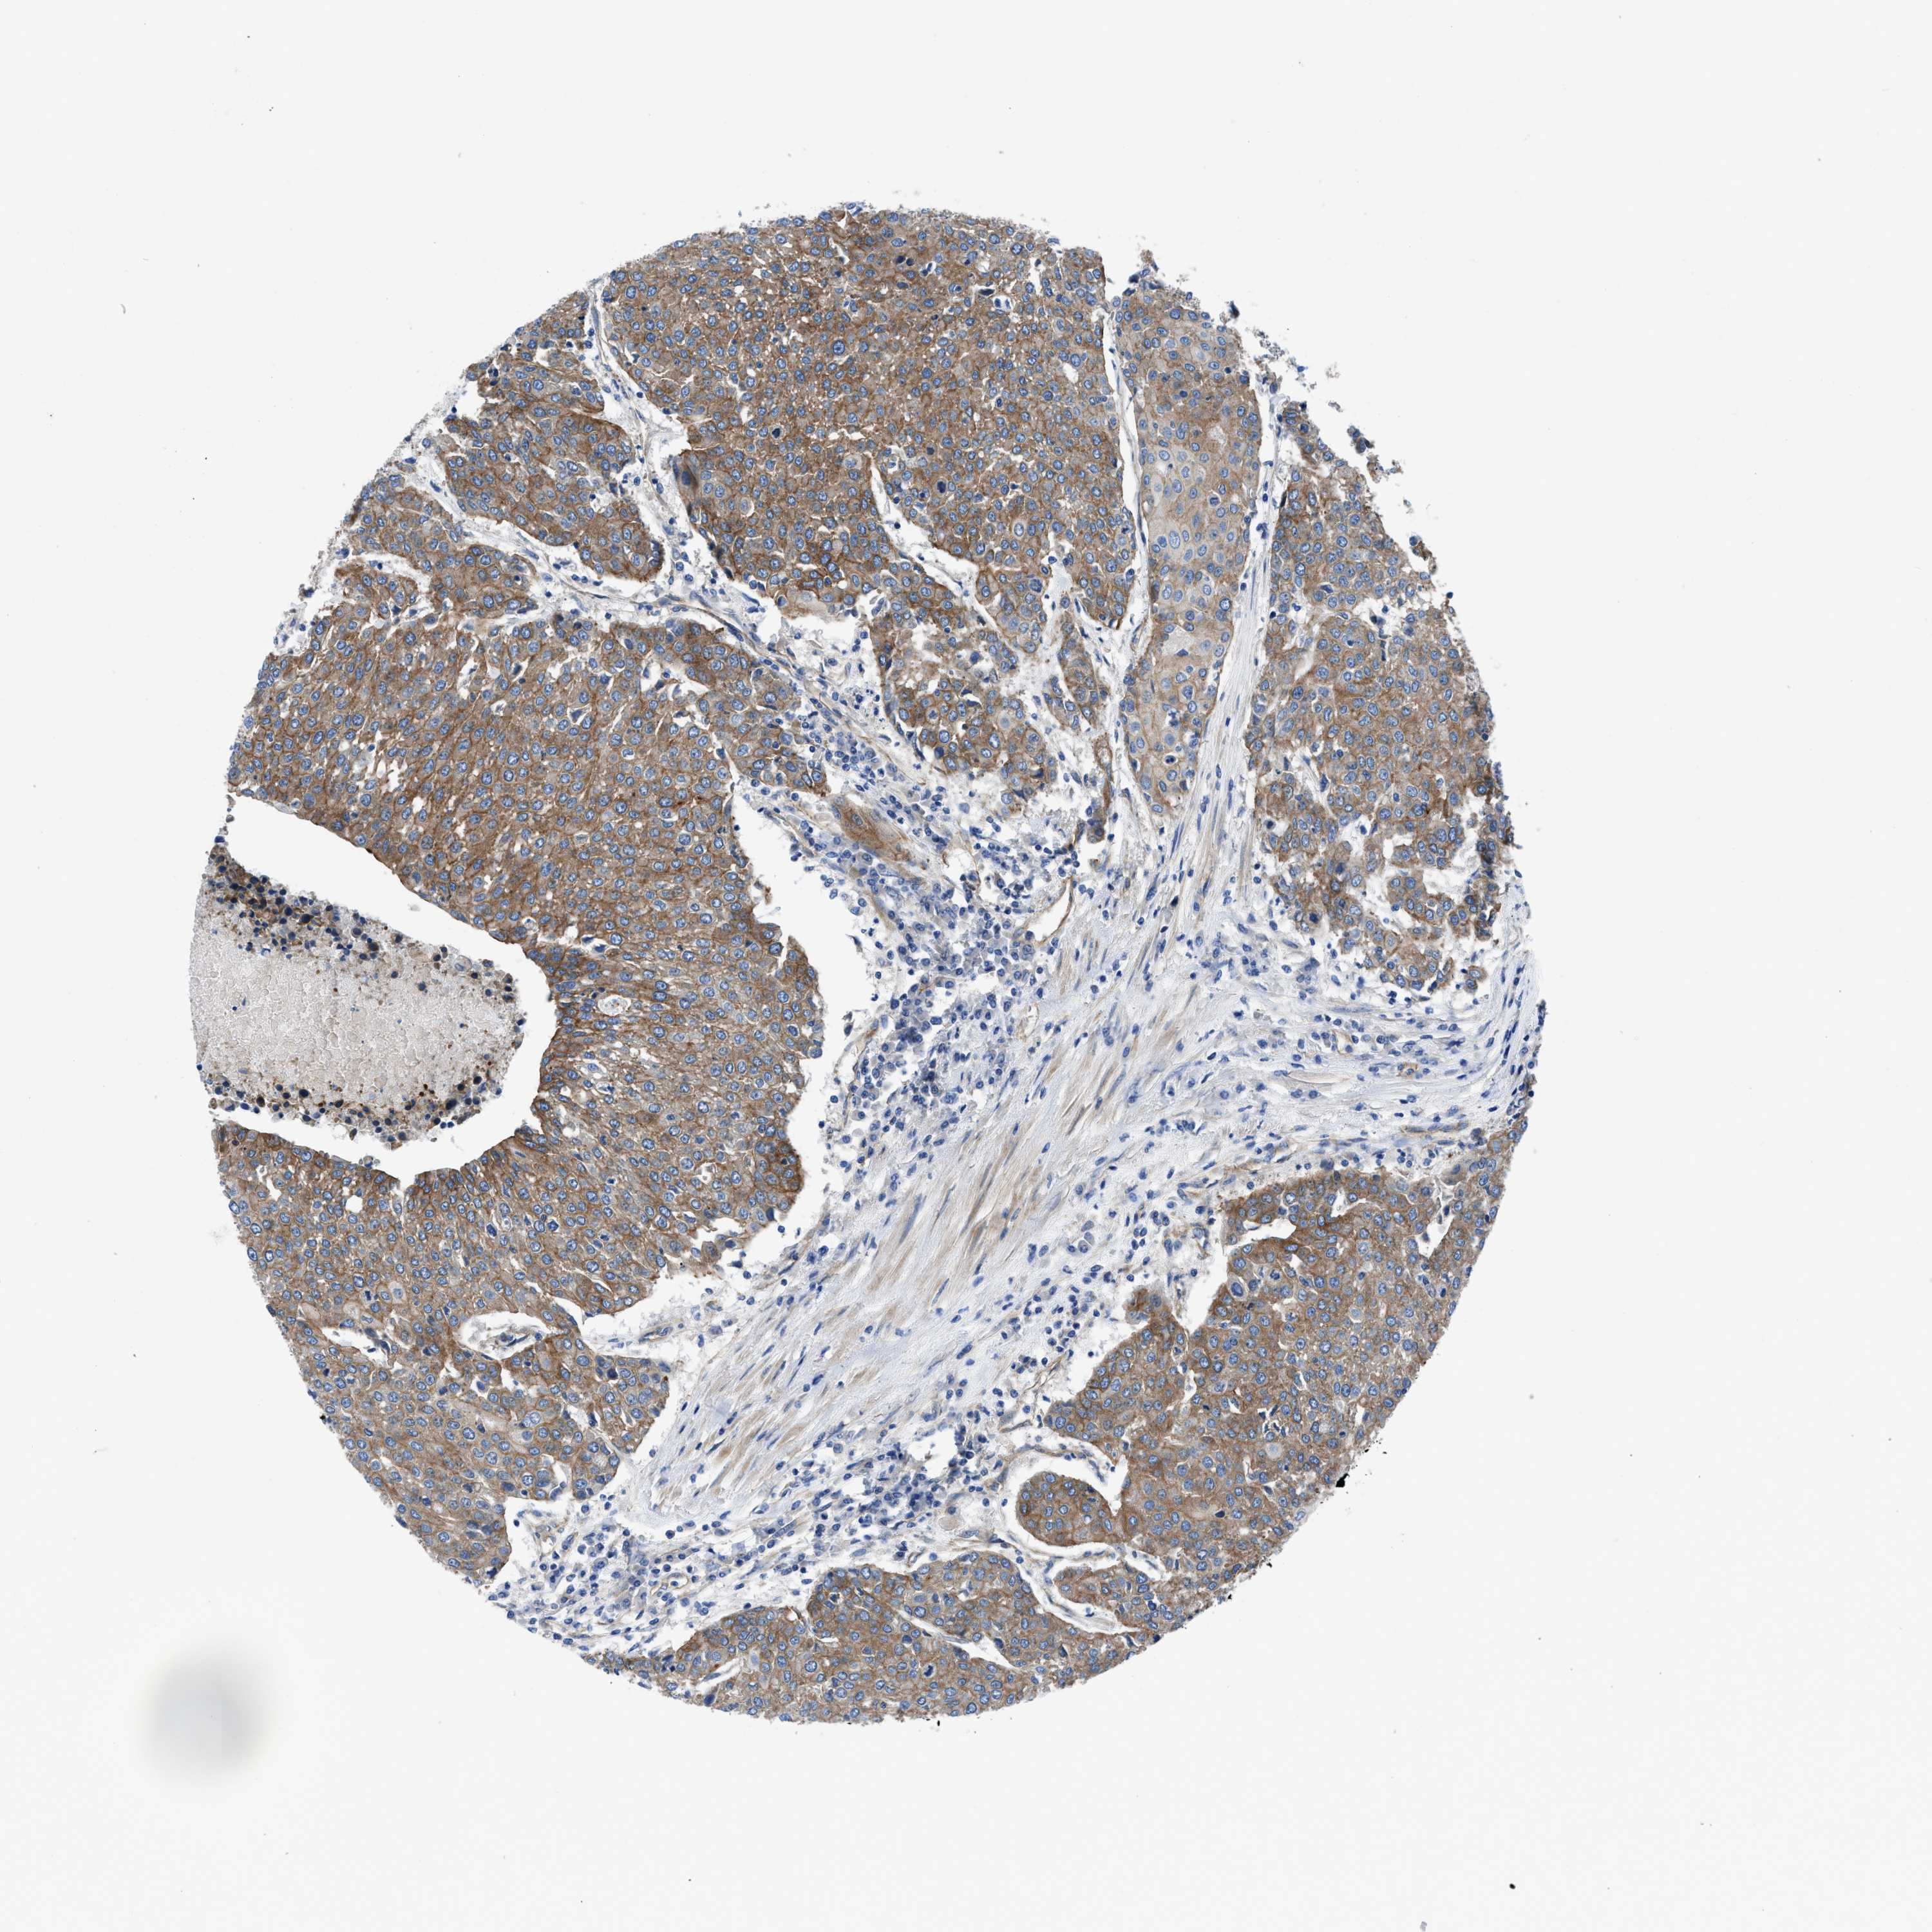

UROTHELIAL CANCER - Protein expressioni

A mouse-over function shows sample information and annotation data. Click on an image to view it in a full screen mode. Samples can be filtered based on level of antibody staining by selecting one or several of the following categories: high, medium, low and not detected. The assay and annotation is described here.

Note that samples used for immunohistochemistry by the Human Protein Atlas do not correspond to samples in the TCGA dataset.

Antibody stainingi

Antibody staining in the annotated cell types in the current human tissue is reported as not detected, low, medium, or high, based on conventional immunohistochemistry profiling in selected tissues. This score is based on the combination of the staining intensity and fraction of stained cells.

Each image is clickable and will lead to virtual microscopy that enables deeper exploration of all samples and also displays staining intensity scores, fraction scores and subcellular localization as well as patient and tissue information for each sample.

Antibody HPA016605

Staining

High

Medium

Low

Not detected

Intensity

Strong

Moderate

Weak

Negative

Quantity

>75%

75%-25%

<25%

None

Location

Nuclear

Cytoplasmic/membranous

Cytoplasmic/membranous,nuclear

Urothelial carcinoma, Low grade

Urothelial carcinoma, High grade